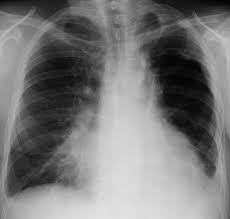

La pneumonie interstitielle, appelée également pneumopathie infiltrante diffuse (pid) et. Dispneea sau respiratia ingreunata in repaus sau agravata de efortul fizic depus. Pneumonia interstitiala la copil debuteaza insidios cu febra, anorexie, cefalee.

Dispneea sau respiratia ingreunata in repaus sau agravata de efortul fizic depus. Die interstitielle pneumonie betrifft nicht die alveolen, sondern das interstitium, d.h. Cel mai intalnit este virusul sincitial am o fetita de 3 luni care are pneumonie interstitiala si care face tratament cu antibiotic de trei.

Pneumonia virală este o infecție acută a parenchimului pulmonar, cu un contrast important între fenomenele generale „zgomotoase, semnele fizice modeste şi modificările radiologice bogate. Principalele semne si simptome ale pneumoniei / pneumopatiei interstitiale sunt: Prezinta un risc sporit in ce priveste aparitia pneumoniei copiii care au o varsta extrem de frageda (cei nascuti prematur), cei care sunt expusi fumului de tigara, cei care prezinta o afectiune cronica (de lunga durata) care afecteaza plamanii.